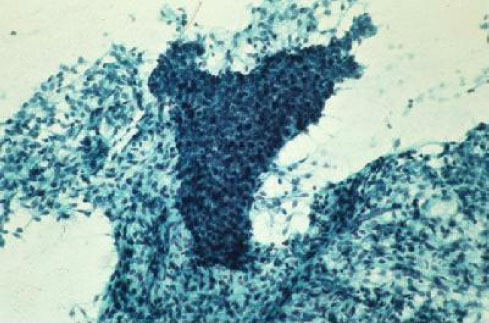

B31-7:心包积液B细胞淋巴瘤

B31-8:心包积液B细胞淋巴瘤

B31-9:心包积液B细胞淋巴瘤